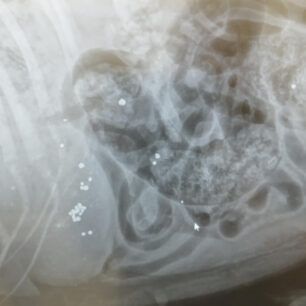

Τελικά οι ακτινογραφίες έδειξαν τι έχει συμβεί. Ο σκύλος είναι πυροβολημένο. Δεκάδες σκάγια εντοπίστηκαν στο σώμα του, στην σπονδυλική στήλη με αποτέλεσμα το ζώο να μην μπορεί όχι μόνο να κινηθεί αλλά και να αφοδεύσει με αποτέλεσμα στο έντερο να έχουν συσσωρευθεί κόπρανα.

Η Ευτυχία Πουρνάρα με αφορμή το περιστατικό επισήμανε τα εξής στις 3 Ιανουαρίου: «ΦΙΛΟΙ ΜΟΥ ΒΟΗΘΗΣΤΕ ΑΥΤΟ ΤΟ ΠΛΑΣΜΑ ΝΑ ΓΙΝΕΙ ΚΑΛΑ ΓΙΑΤΙ ΕΝΩ ΜΟΥ ΕΙΠΑΝ ΠΡΕΠΕΙ ΝΑ ΤΟ ΧΤΥΠΗΣΕ ΑΥΤΟΚΙΝΗΤΟ  ΣΥΓΚΛΟΝΙΣΤΙΚΑ ΟΤΑΝ ΟΙ ΑΚΤΙΝΟΓΡΑΦΙΕΣ ΔΕΙΞΑΝ ΟΤΙ ΤΟ ΚΟΡΜΑΚΙ ΤΟΥ ΣΚΥΛΑΚΟΥ ΕΙΤΑΝ ΓΕΜΑΤΟ ΣΚΑΓΙΑ ΔΙΑΣΠΟΡΑΣ ΕΝΑ ΤΟ ΒΡΕΙΚΕ ΣΤΗΝ ΣΠΟΝΔΥΛΙΚΗ ΣΤΥΛΗ Ο ΓΙΑΤΡΟΣ ΜΟΥ ΚΥΡΙΟΣ ΚΑΡΑΜΗΤΡΟΣ ΜΟΥ ΕΔΩΣΕ ΑΓΩΓΗ  ΤΟ ΖΩΟ ΔΕΝ ΜΠΟΡΟΥΣΕ ΝΑ ΑΦΟΔΕΥΣΗ ΚΑΙ ΠΡΙΣΤΗΚΕ ΚΑΝΟΥΜΕ ΑΓΩΝΑ ΝΑ ΤΟ ΒΟΗΘΗΣΟΥΜΕ ΤΟ ΚΑΛΟ ΕΙΝΑΙ ΟΤΙ ΑΙΣΘΑΝΕΤΑΙ ΤΑ ΠΟΔΑΡΑΚΙΑ ΤΟΥ ΘΑ ΣΑΣ ΠΩ ΝΕΟΤΕΡΑ ΤΟ ΚΑΘΑΡΜΑ ΠΟΥ ΤΟ ΠΥΡΟΒΟΛΗΣΕ  ΕΥΧΩΜΕ ΑΥΤΟ ΠΟΥ ΕΚΑΝΕ ΝΑ ΤΟ ΒΡΕΙ ΜΠΡΟΣΤΑ ΤΟΥ ΜΗΝ ΞΕΧΝΑΤΕ ΒΟΗΘΗΣΤΕ  ΕΧΩ ΑΓΩΝΑ ΜΠΡΟΣΤΑ ΜΟΥ ΓΙΑ ΝΑ ΣΩΘΕΙ ΣΤΕΙΛΤΕ ΜΗΝΝΥΜΑ ΣΤΟ ΜΕΣΣΕΝΤΖΕΡ  ΕΥΧΑΡΙΣΤΩ ΠΟΛΥ ΤΗΛ 6946348888 ΚΙΛΚΙΣ».